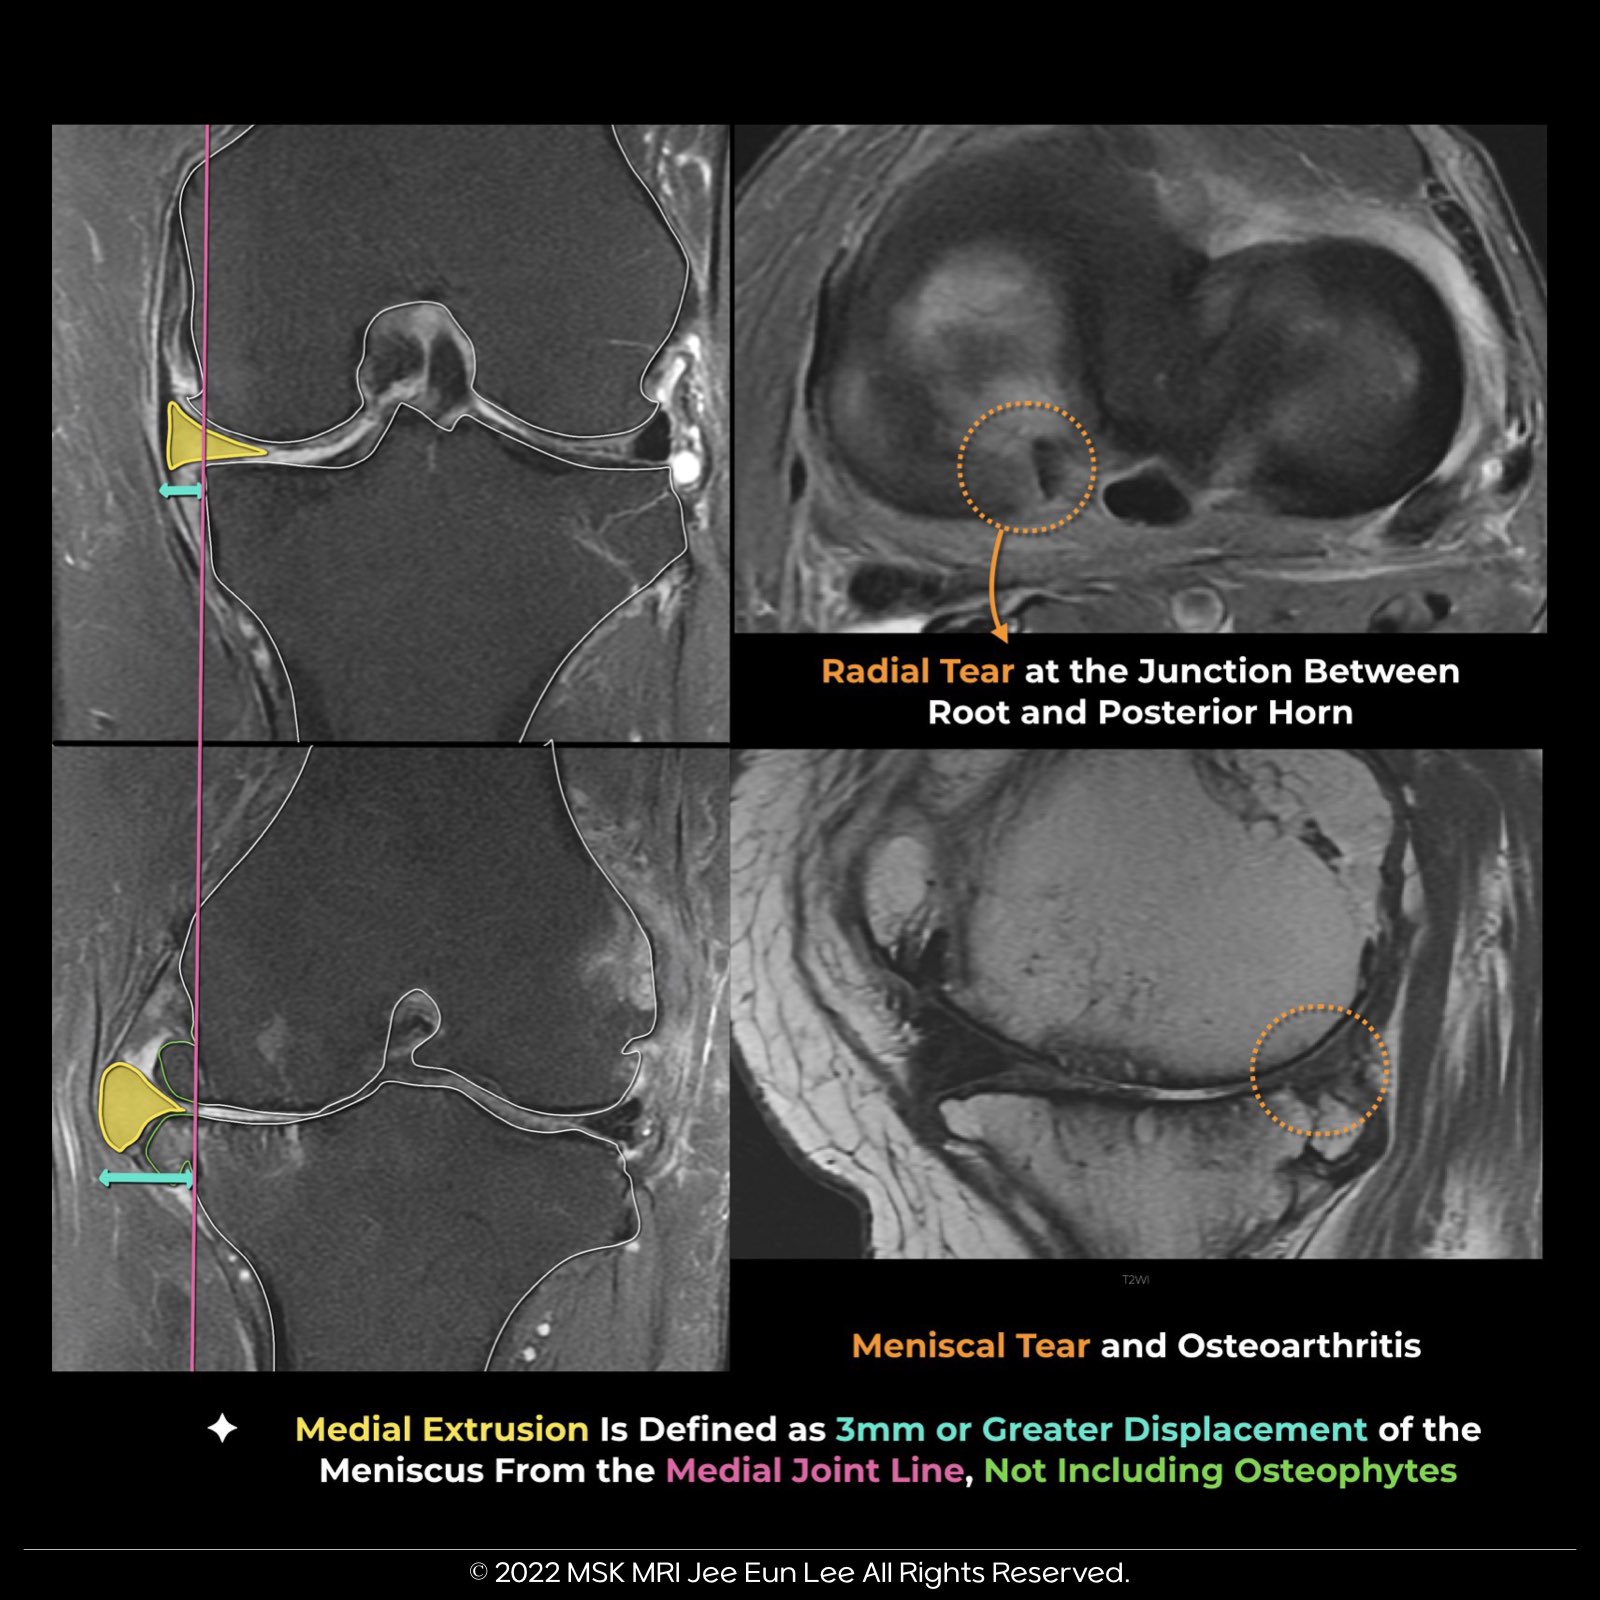

- Meniscal extrusion occurs when the meniscus extends 3 mm or more beyond the tibial plateau edge.

- Substantial medial meniscus extrusion (> 3 mm) indicates severe meniscal issues like degeneration, extensive tears, and root involvement.

- Extrusion is commonly associated with posterior root tears but can also be caused by large radial tears, osteoarthritis, and knee malalignment.

- Orthopedic literature commonly indicates that meniscus extrusion is often caused by medial meniscus (MM) posterior root tears. However, recent evidence suggests the reverse may also be true, where meniscus extrusion could lead to root tears.

- This is based on observations from serial imaging studies showing that disruption of the meniscotibial ligament and meniscus extrusion may increase stress at the root, potentially causing a tear.

- Consequently, there’s growing interest in surgically reducing meniscus extrusion through meniscotibial ligament repair to address this issue.